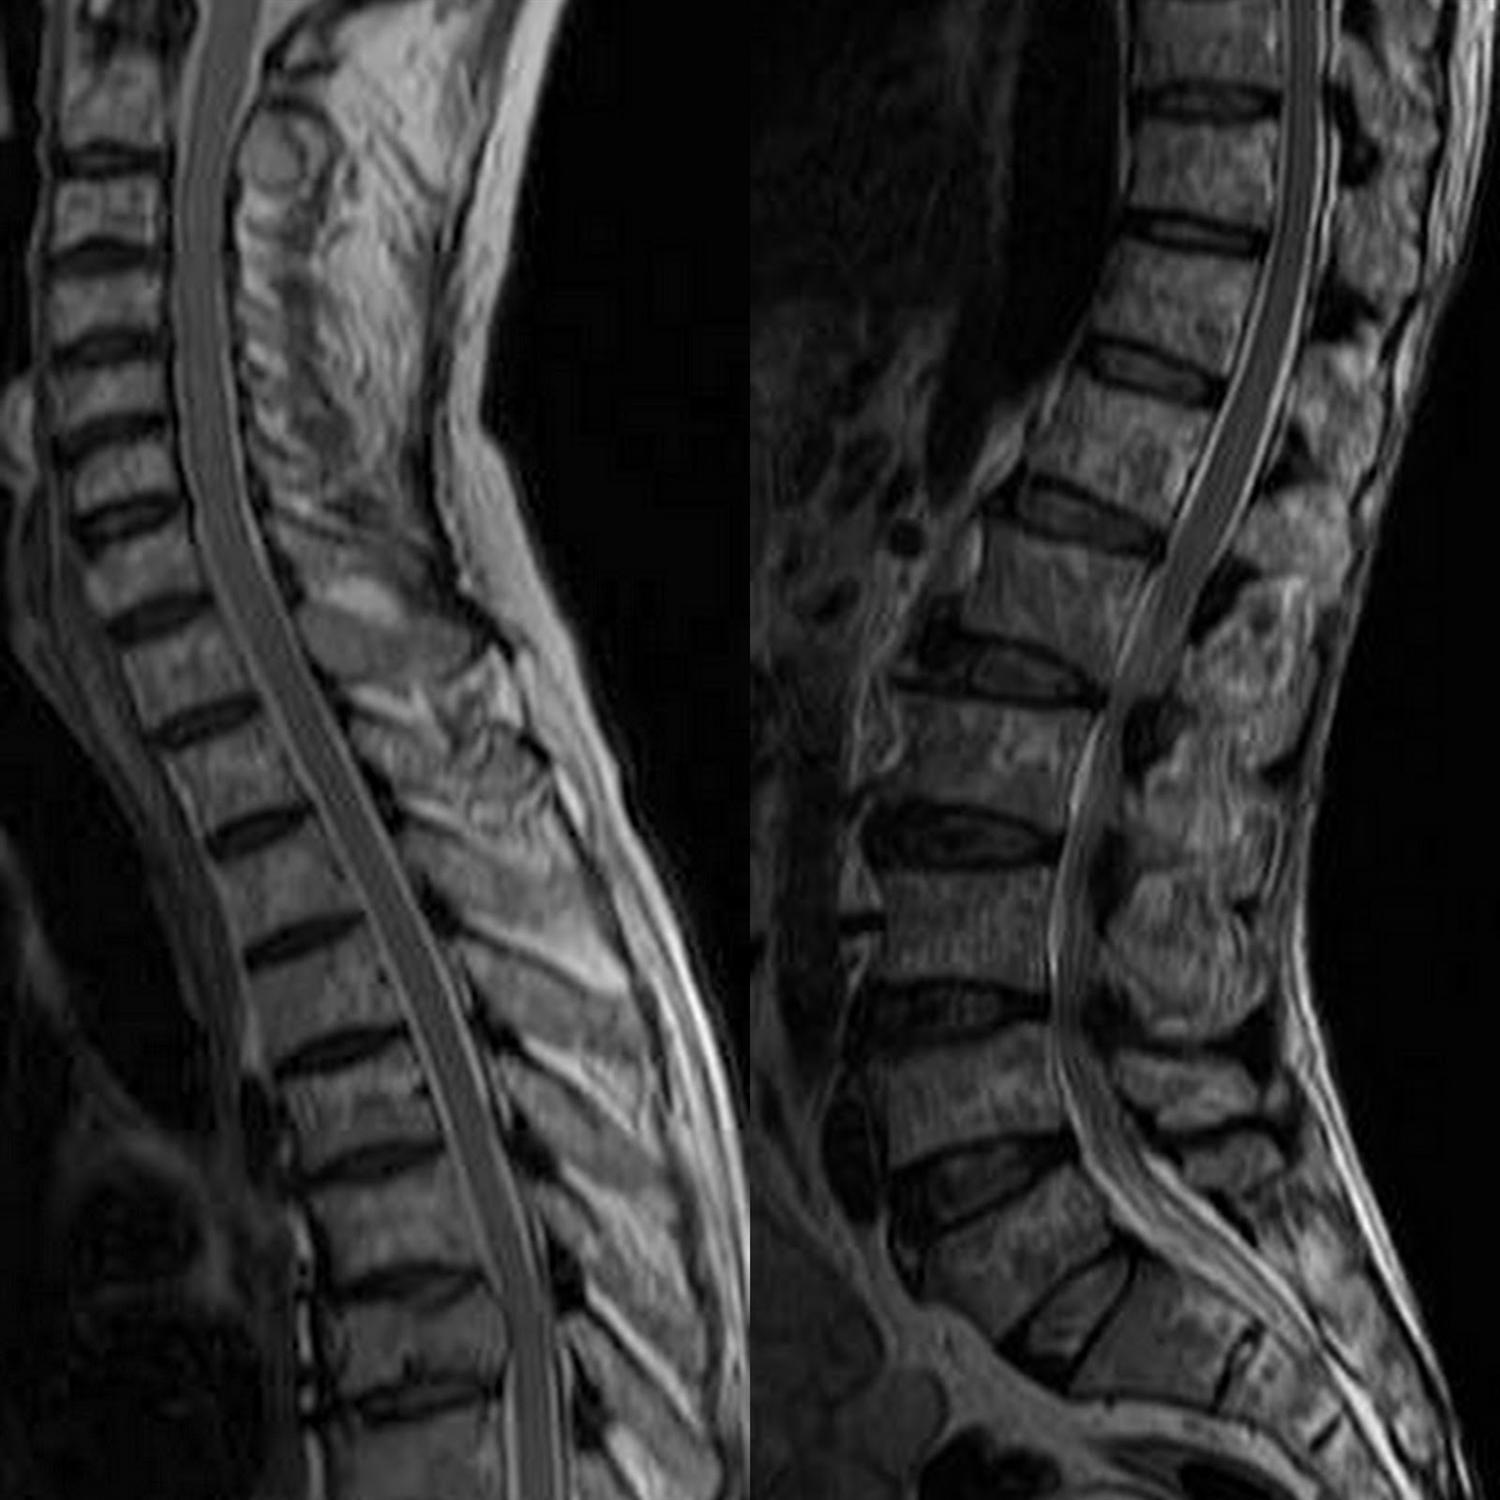

MRI examination showing (A) a dumbbellshaped lesion with demonstration Salt And Pepper Appearance Mri five different infiltration patterns have been described on mri with the “salt and pepper” pattern of inhomogeneous bone marrow infiltration. the salt and pepper sign is used to refer to a speckled appearance of tissue on imaging. Paragangliomas, also known as glomus tumors, arise from. they also often exhibit a characteristic “salt and pepper” appearance on mr.. Salt And Pepper Appearance Mri.

Wholebody MRI of a 45yearold patient with multiple myeloma. The STIR Salt And Pepper Appearance Mri Paragangliomas, also known as glomus tumors, arise from. ct and mri findings of the vagal paraganglioma are similar to those of the carotid body. the salt and pepper sign is used to describe a typical mri appearance of some highly vascular tumors that contain. the salt and pepper sign is used to refer to a speckled appearance. Salt And Pepper Appearance Mri.

28 Diffusely Abnormal Marrow Signal within the Vertebrae on MRI Salt And Pepper Appearance Mri they also often exhibit a characteristic “salt and pepper” appearance on mr. the salt and pepper appearance, first described in 1987 by olsen et al, is a characteristic imaging feature of. It is used in many contexts,. ct and mri findings of the vagal paraganglioma are similar to those of the carotid body. the salt and. Salt And Pepper Appearance Mri.